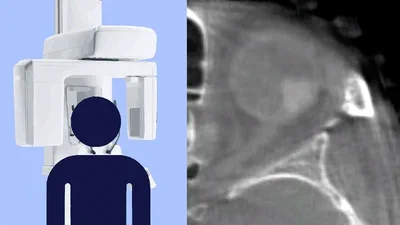

Dutch Research Council NWO grant awarded for developing an ocular cone-beam CT scanner

Project to develop ocular CBCT funded

Our grant application to develop an ocular cone-beam CT scanner has been awarded by the Dutch Research Council.